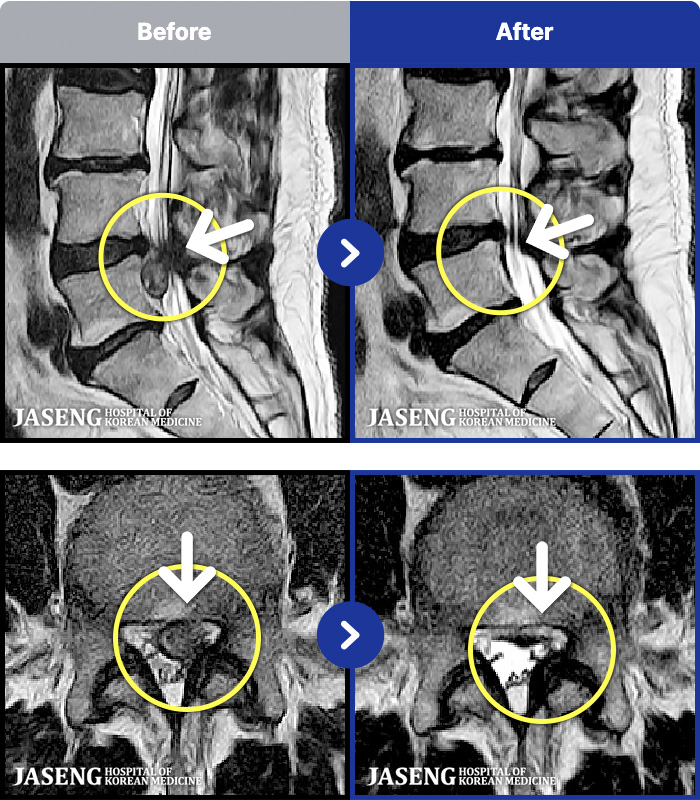

MRI ũ ʸ Ȯϼ.

[뱸] 19.11.28~25.05.06